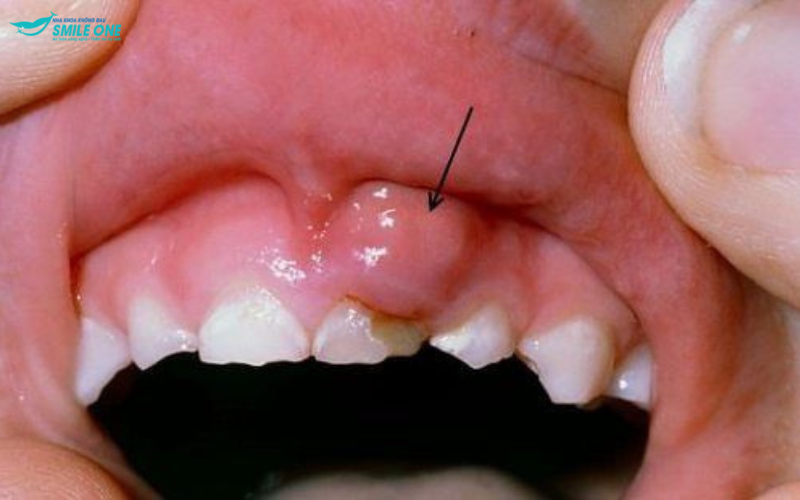

► Khi viêm nha chu ở giai đoạn nặng, xuất hiện mủ, có chất dịch chảy ra ở nướu răng.

– Hình thành túi mủ giữa răng và nướu